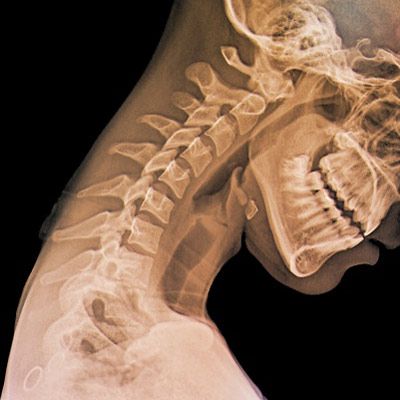

成人の頭の重さは4.5-5.5キログラムだ。直立の姿勢の時、頭部の重さは脊柱の上に圧力となってのしかかる。研究によると、首を前に倒す動作は、頸椎と脊柱にかかる圧力を増加させてしまう。頭部を前に15度倒すと圧力は12キログラムまで増加し、30度倒すと18キログラムに、45度倒すと22キログラムに、60度倒すと27キログラムにまで増加し、10歳の児童を肩の上に乗せているのと同じくらいになるというから驚きである。

ニューヨーク脊椎外科・リハビリ医学センターの脊椎外科主任のKenneth K Hansraj医師は、「これらの圧力により頸部に痛みが出るほか、頸部周囲の筋肉や腱、じん帯にも圧力が伝わる」と述べている。